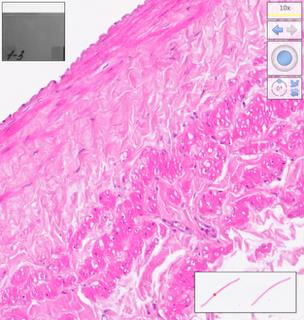

Histological examination was performed on days 7, 14, 21, 28, 35, 42, 49, 56, 63, 70, 77, 84 after homograft collection, ten arterial and ten venous preparations respectively. Twelve comparison groups of arterial and venous homografts were obtained. One hundred twenty arterial and 120 venous specimens were studied. The number of myocyte nuclei in the middle layer of homografts was estimated using automatic counting in the Image-PRO Plus 6.0 program (Figure 1) and recalculation of the obtained values per 0.01 mm2 (10,000 μm2) of the area of the middle layer of the vessel homograft wall. Counting was performed in 1 field of view at medium magnification (×100) using digital processing to visualize muscle cell nuclei. The software used was NDP.view2 (U12388-01; Hamamatsu Photonics KK).

Fig. 1. The stages of digital processing of the homograph wall (magnified ×100).